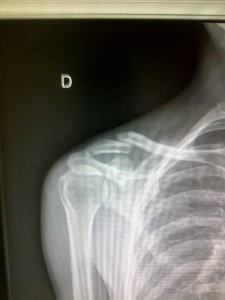

Wesley Sulzberger es la segunda baja de la Vuelta a España, tras la de Koldo Fernández de Larrea. A pesar de haber terminado la 4ª etapa en la plaza 195ª y penúltima a 14’21» del ganador Dani Moreno, el australiano de Tasmania llegó con una fractura de clavícula y otras más pequeña en su codo, que le impedirán seguir en carrera, tras caerse en el . Tras la etapa el equipo Orica le llevó a un hospital donde las radiografías confirmaron el fatal pronóstico.

«No me había roto nada antes», agregó. «Me dolía mucho, pero no quería abandonar si no tenía fracturas. Cuando vi la radiografía comprendí lo que había sucedido y que no iba a salir mañana (por hoy). También tengo una pequeña fractura en el codo».